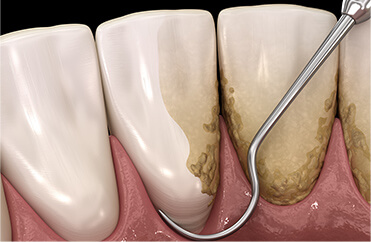

歯周病は、歯垢(プラーク)という細菌の塊が歯と歯ぐきの間の歯周ポケットに溜まり、細菌が繁殖することによって引き起こされます。歯垢は放置すると石灰化して歯石となり、日々の歯みがきでは除去できなくなる上、歯周ポケットを深くする原因となり、歯周病を進行させてしまいます。

歯の表面に付着した歯垢や歯石をスケーラーを用いて取り除きます。

スケーラーを用いて歯周ポケットの内部や歯根に付着した歯石を取り除き、歯周病の進行を抑えます。